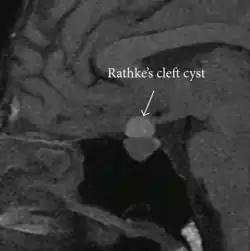

Rathke's cleft cyst in a 53-year-old man with a pituitary adenoma and acromegaly |

A Rathke's cleft cyst is a benign growth on the pituitary gland in the brain, specifically a mucin-filled[1] cyst in the posterior portion of the anterior pituitary gland.[2][3] It occurs when the Rathke's pouch does not develop properly and ranges in size from 2 to 40 mm in diameter.[3]